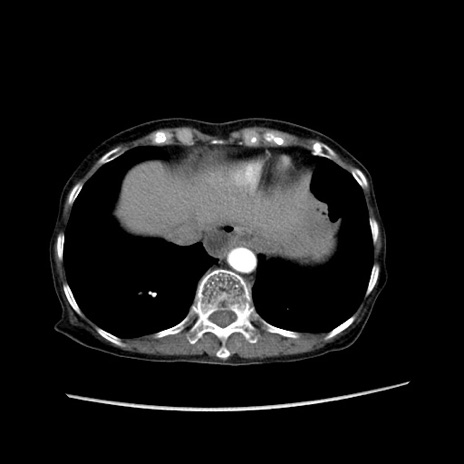

症例25(横断像)

【症例】80歳代女性

【主訴】胸のつかえ感

【現病歴】約9時間前に食後から胸のつかえた感じあり、嘔吐あり、来院。

【既往歴】胃癌(全摘)、胆摘、虫垂炎

【身体所見】心窩部に圧痛あり、反跳痛なし。

【データ】WBC 5700、CRP 0.05